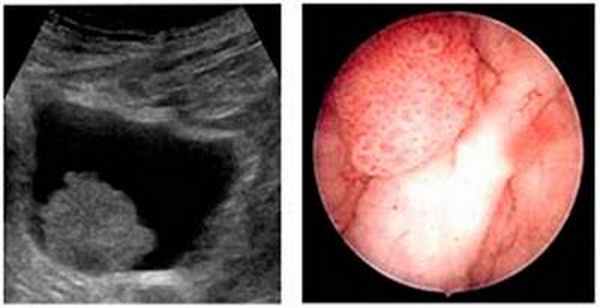

Выявить опухоль в мочевом пузыре можно с помощью ультразвукового исследования. Обязательным условием выполнения УЗИ мочевого пузыря, является хорошо наполненный мочевой пузырь, для чего за 30-60 мин до исследования следует постепенно выпить около 500 мл жидкости.

Цистоскопия – основной метод диагностики рака мочевого пузыря

Цистоскопия – основной метод диагностики рака мочевого пузыря. Это процедура, в ходе которой уролог с помощью специального оптического прибора производит осмотр внутренней поверхности мочевого пузыря.

Цистоскопия позволяет врачу увидеть опухоль, а также взять кусочек опухоли для гистологического исследования. Это исследование может быть не очень приятным, так как необходимо ввести цистоскоп в мочевой пузырь через мочеиспускательный канал.

Наиболее частой формой рака мочевого пузыря является переходно-клеточный рак (95%) (развивающийся из переходного эпителия мочевых путей), реже встречаются плоскоклеточный рак и аденокарцинома (опухоль, происходящая и построенная из железистого эпителия). Опухоль в мочевом пузыре может быть в виде папиллярных разрастаний («цветная капуста») или солидной, изъязвлённой, инвазирующей опухоли. По течению процесса и применяемому лечению различают рак мочевого пузыря in situ, мышечнонеинвазивный рак (Т1-2) и инвазирувный рак с прорастанием только в мышечный слой и окружающие ткани (ТЗ-4).

Главным методом диагностики рака мочевого пузыря, которое проводится обычно на заключительном этапе является цистоскопия с биопсией и гистологическимисследованием.